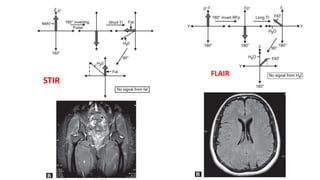

• STIR( short tow inversion recovery) : use shorter TI 80- 150 ms .

• It is very useful to suppress the signal of fat .

• FLAIR( fluid level attenuation inversion recovery ) : It use longer TI

time range between 1500 -2500 ms)..

• It used to suppress the fluid signal.

STIR

1. Short TI of 80-150 ms used.

2. Combined T1 and T2 weighting is

obtained

3. Fat, white matter can be

suppressed

4. Mainly used in body imaging

5. Cannot be used in post-contrast

imaging as short T1 tissue are

suppressed and contrast shortens

T1 of tissues taking up contrast.

FLAIR

1. Long TI of 1500-2500 ms is

used.

2. Heavily T2-weighted images

are obtained.

3. CSF, water is suppressed

4. Used in neuroimaging

5. Can be used in post-contrast

imaging.